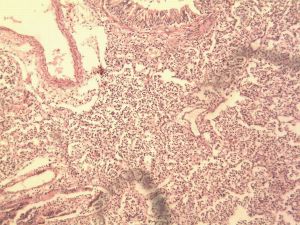

鐵鏽色痰主要由肺炎鏈球菌引起的累及肺大葉的大部或全部,以肺泡內瀰漫性纖維素滲出為主的急性炎症。除肺炎球菌外,肺炎桿菌、金黃色葡萄球菌、溶血性鏈球菌、流感嗜血桿菌也可以引起大葉性肺炎。受寒、疲勞、醉酒、感冒、麻醉可以成為大葉性肺炎的誘因。此時,呼吸道的防禦功能被削弱,機體抵抗力降低,容易發生細菌感染,細菌侵入肺泡內,在其內繁殖,特別是形成的漿液性滲出物更加有利於細菌繁殖,引起肺組織的變態反應,肺泡間隔毛細血管擴張通透性增高,並使細菌通過肺泡間孔或呼吸性支氣管迅速向鄰近肺組織蔓延,從而波及整個大葉,在大葉間的蔓延則是帶菌滲出液經葉支氣管播散所致。

4.胸部X線檢查早期為均勻的淡影,大葉實變為大片均勻緻密陰影,多呈葉、段分布。